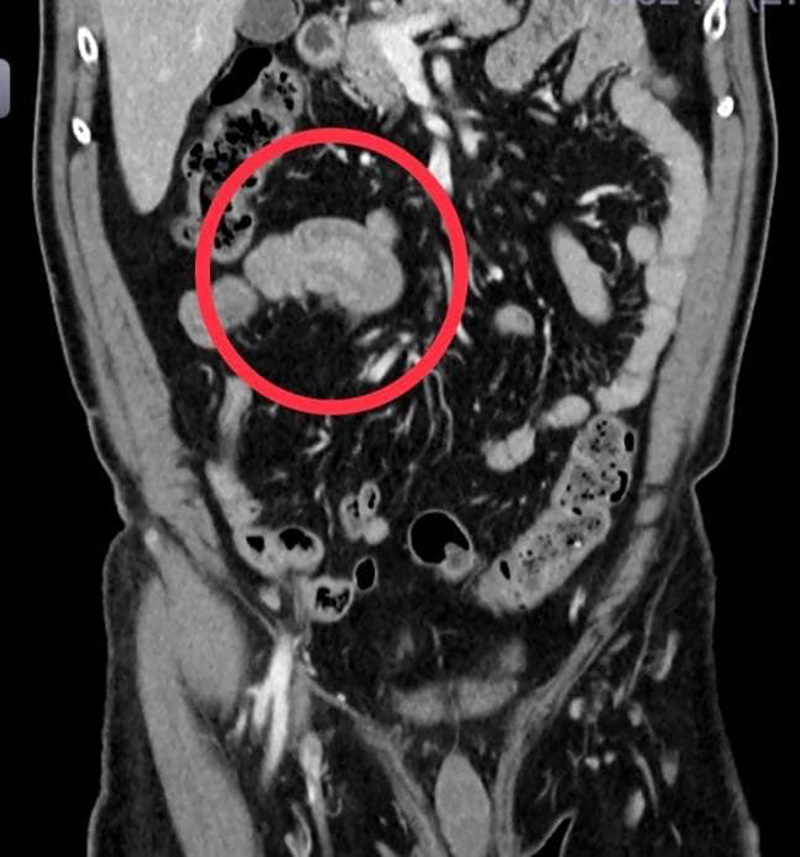

แพทย์ห้องฉุกเฉิน เห็นว่าผู้ป่วยเป็นผู้สูงอายุและเป็นมานาน ควรจะได้รับการตรวจวินิจฉัยโดยละเอียด จึงปรึกษาอายุรแพทย์ ศัลยแพทย์ และรังสีแพทย์ ไปพร้อม ๆ กัน จนได้ภาพรังสีจากเอกซเรย์คอมพิวเตอร์ออกมา พบว่ามีส่วนของลำไส้เล็กส่วนปลายกลืนกัน จึงวางแผนรักษาโดยการผ่าตัดทันที